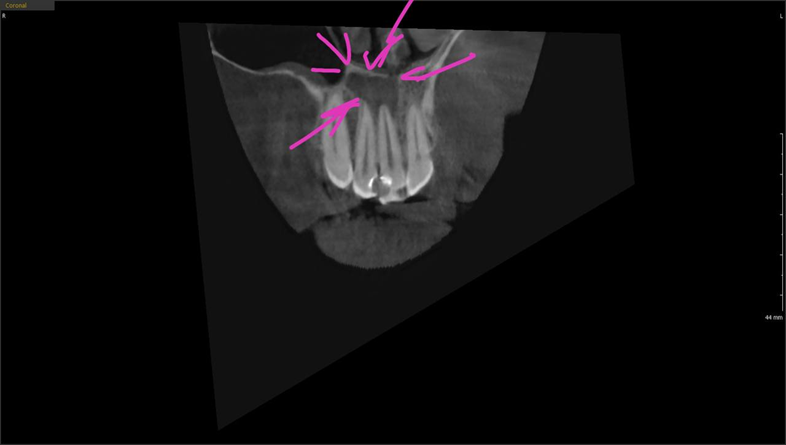

«Взорваться» и потребовать срочного лечения киста могла в любой момент в какой-нибудь условной Норвегии. А неотложная стоматология, да ещё и в чужой стране, — удовольствие не из комфортных. Она росла и была уже настолько велика, что выглядела на снимке как воспалительный очаг в области двух зубов. Откуда всё началось, было не очень-то очевидно, так что самой первой задачей для меня было определиться, с какого зуба начинать лечение. Я даже побаивался, что, возможно, не получится его спасти. Но, как бы то ни было, мы постарались успокоить Илью и пообещать, что всеми силами будем сохранять его зубы.

Тёмная область и есть рентгенологическая картина кисты

Саму клиническую картину мы получили, только когда сделали томограмму и прицельные снимки.

Зуб с кистой на прицельном снимке